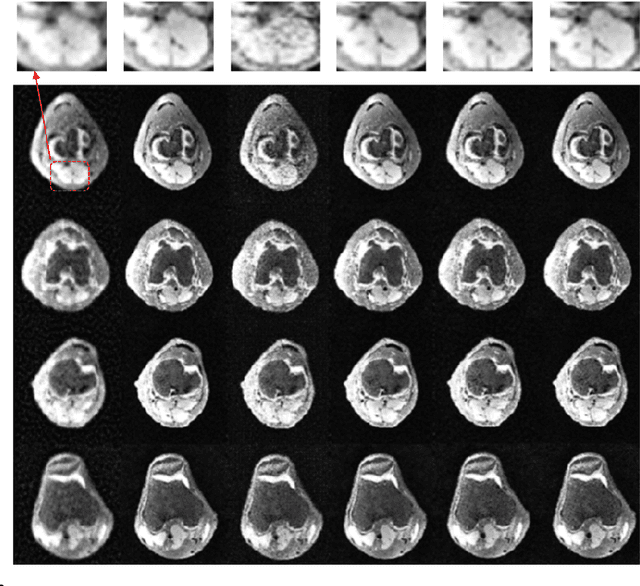

Abstract:Recovering high-quality images from limited sensory data is a challenging computer vision problem that has received significant attention in recent years. In particular, solutions based on deep learning, ranging from autoencoders to generative models, have been especially effective. However, comparatively little work has centered on the robustness of such reconstructions in terms of the generation of realistic image artifacts (known as hallucinations) and quantifying uncertainty. In this work, we develop experimental methods to address these concerns, utilizing a variational autoencoder-based generative adversarial network (VAE-GAN) as a probabilistic image recovery algorithm. We evaluate the model's output distribution statistically by exploring the variance, bias, and error associated with generated reconstructions. Furthermore, we perform eigen analysis by examining the Jacobians of outputs with respect to the aliased inputs to more accurately determine which input components can be responsible for deteriorated output quality. Experiments were carried out using a dataset of Knee MRI images, and our results indicate factors such as sampling rate, acquisition model, and loss function impact the model's robustness. We also conclude that a wise choice of hyperparameters can lead to the robust recovery of MRI images.